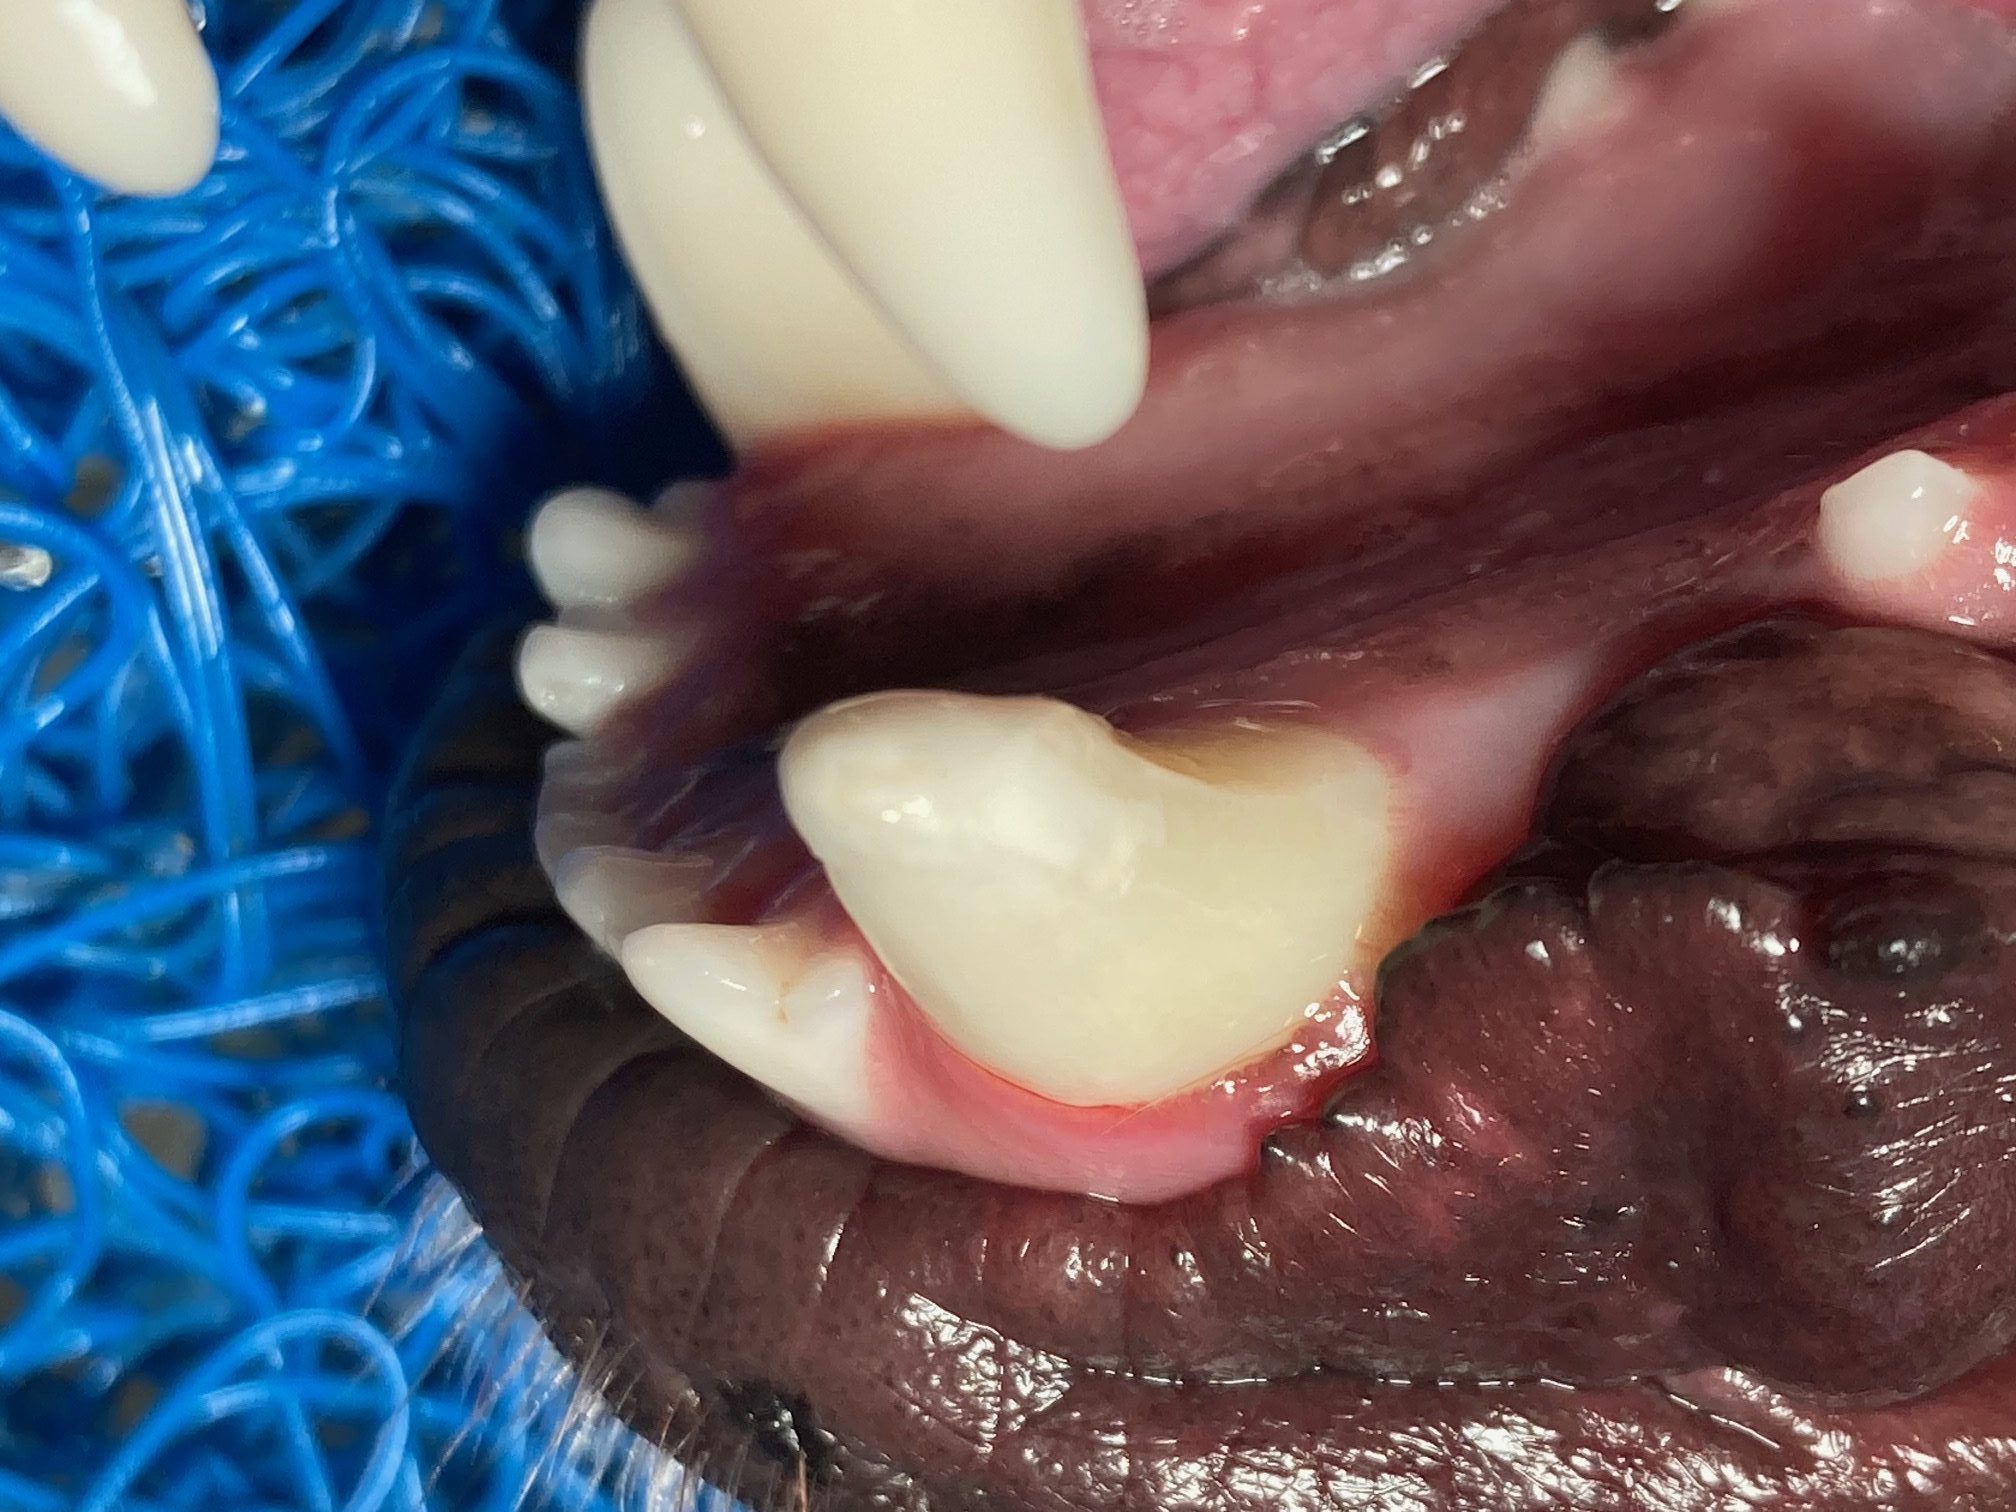

• Fogkő eltávolítás és polirozás

• Foghúzás

• Fogmegtartó kezelések